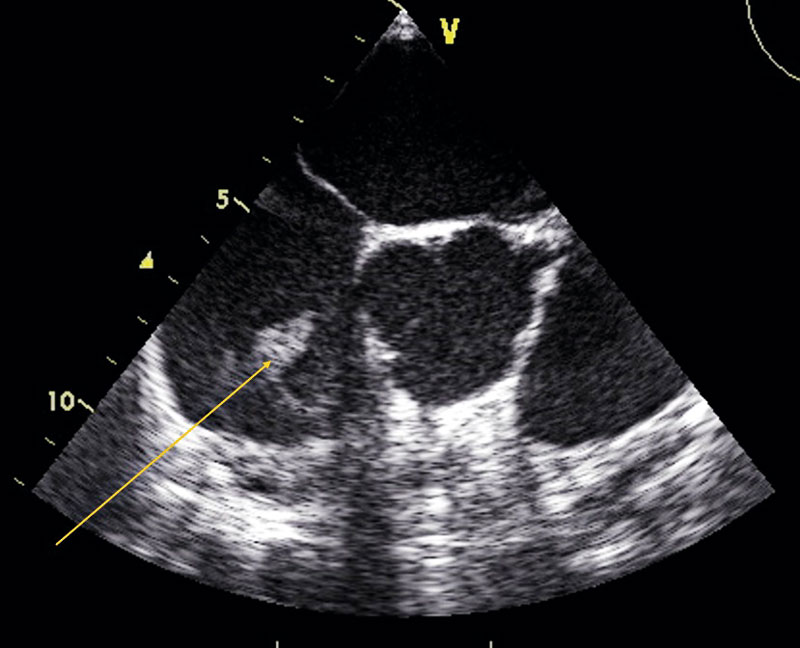

Transesofagal fyrrumsvy: vegetation på trikuspidalisklaffen.

Transesofagal kortaxelvy: vegetation på trikuspidalisklaffen.